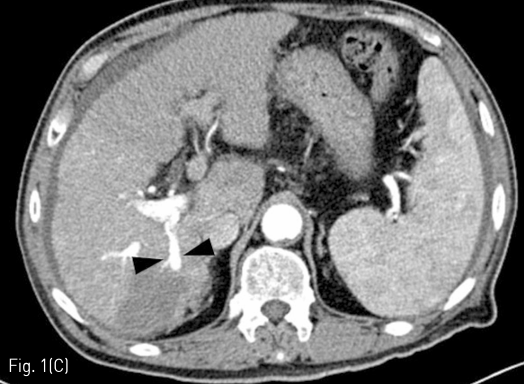

Fig 1C

(C-D) RFA was conducted and follow-up liver CT was performed a month after the treatment. On an arterial phase image, the right posterior portal vein (arrow heads) showed hyperenhancement as much as the adjacent hepatic artery.